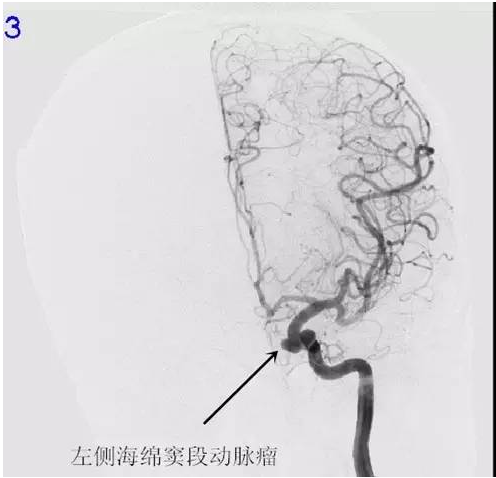

周阿姨,63岁,突发性头痛20小时,就诊当地医院CT示:蛛网膜下腔出血。为求进一步治疗,来我院就诊。入院后完善相关检查,检查提示:右侧后交通动脉瘤,左侧颈内动脉动脉瘤,行介入栓塞治疗去除动脉瘤。病人经系统治疗后颅内血肿完全吸收,头痛缓解,康复出院。